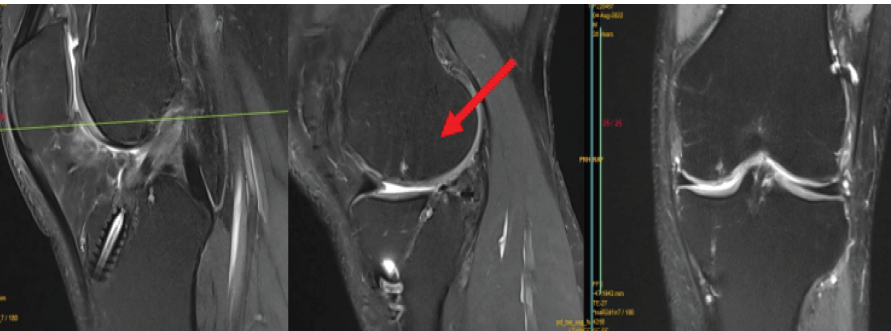

His magnetic resonance imaging (MRI) left knee revealed complete ACL tear from femoral site with MMRT with infolding of meniscus lying in meniscotibial recess and grade 4 chondral defect at medial femoral condyle of size 1.5 × 1.5 cm (Fig. 1).

Figure 1: Anterior cruciate ligament tear, medial meniscus root tear, and cartilage defect over medial femur condyle.